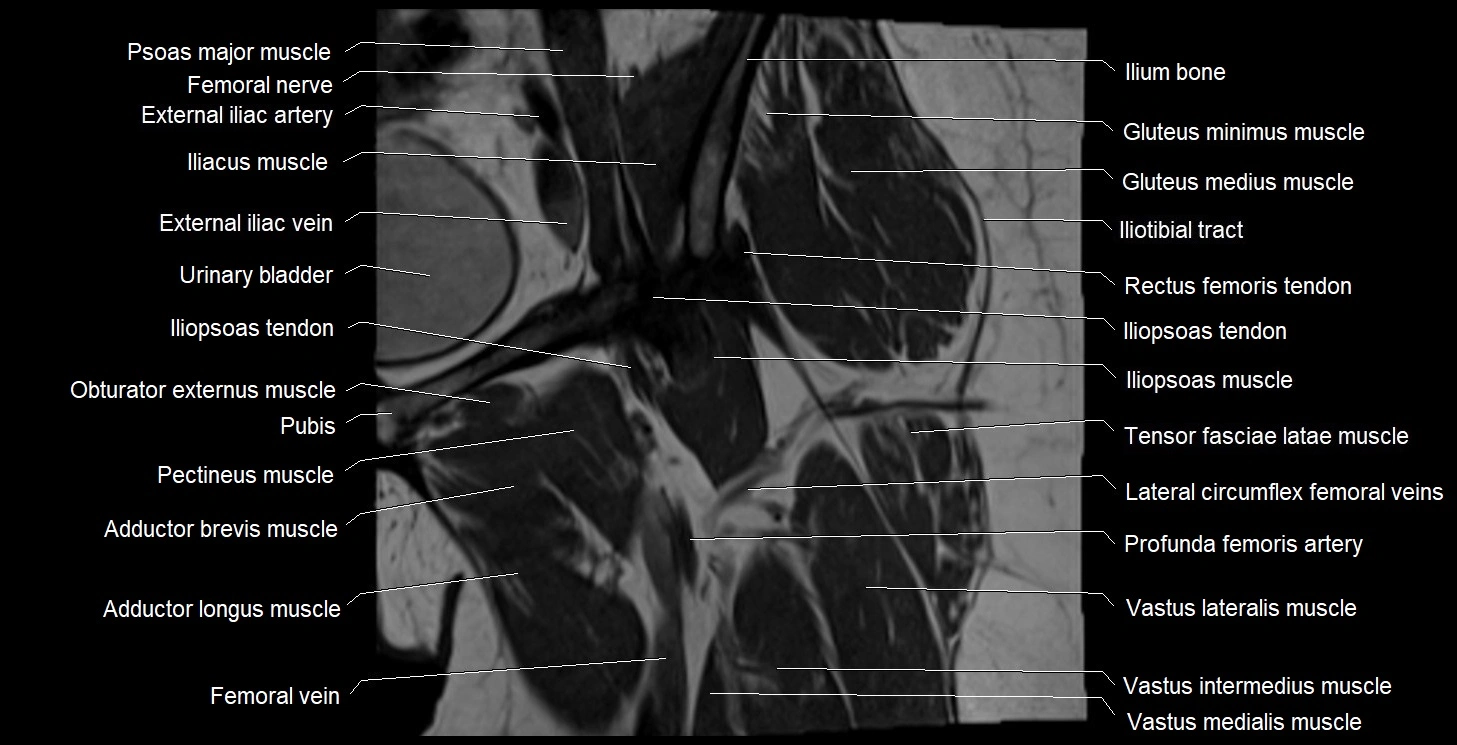

- External iliac artery

- External iliac vein

- Femoral nerve

- Femoral vein

- Gluteus medius muscle

- Gluteus minimus muscle

- Iliopsoas muscle

- Iliopsoas tendon

- Iliotibial tract

- Ilium bone

- Lateral circumflex femoral artery

- Lateral circumflex femoral veins

- Levator ani muscle

- Pectineus muscle

- Psoas major muscle

- Rectus femoris muscle

- Rectus femoris tendon (Proximal tendon of rectus femoris)

- Tensor fasciae latae muscle

- Vastus intermedius muscle

- Vastus lateralis muscle

- Vastus medialis muscle

- great saphenous vein